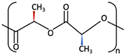

| 1 | PGA |  [39] [39] | High [29] | High [59] | − [59] | 4–12 months [60] | Tissue engineering. Drug-delivery systems [61] | |

| PLA | PLLA |  [62] [62] | High [63] | High [64] | − [51] | > 3.5 years [65] | Tissue engineering. Drug-delivery systems. Fixation devices [66] | |

| PDLA |  [62] [62] | High [63] | High [64] | − [64] | Longer than PLLA [34] | Tissue engineering. Drug-delivery systems, [66] | ||

| PDLLA |  [62] [62] | Lower than PLLA [37] | High [64] | − [64] | 12–30 months [37] | Tissue engineering. Drug-delivery systems [66] | ||

| 2 | PLLA/PGA |  [67] [67] | High [37] | High [68] | − [50] | 12–18 months [44] | Tissue engineering. Drug-delivery systems. Fixation devices [66] | |

| 3 | u-HA/PDLLA | Ca10(PO4)6(OH)2 +  | Low [54] | High [55] | + [56] | 12–18 months [69] | Tissue engineering. Fixation devices [70] | |

| u-HA/PLLA | Ca10(PO4)6(OH)2 +  | Higher than PLLA [19] | High [19] | + [19] | > 5 years [49] | Tissue engineering. Fixation devices [70] | ||

| 4 | u-HA/PLLA/PGA | Ca10(PO4)6(OH)2 +  | Similar to u-HA/PLLA [71] | High [72] | + [71] | 2–3 years [73] | Tissue engineering. Fixation devices [73] | |